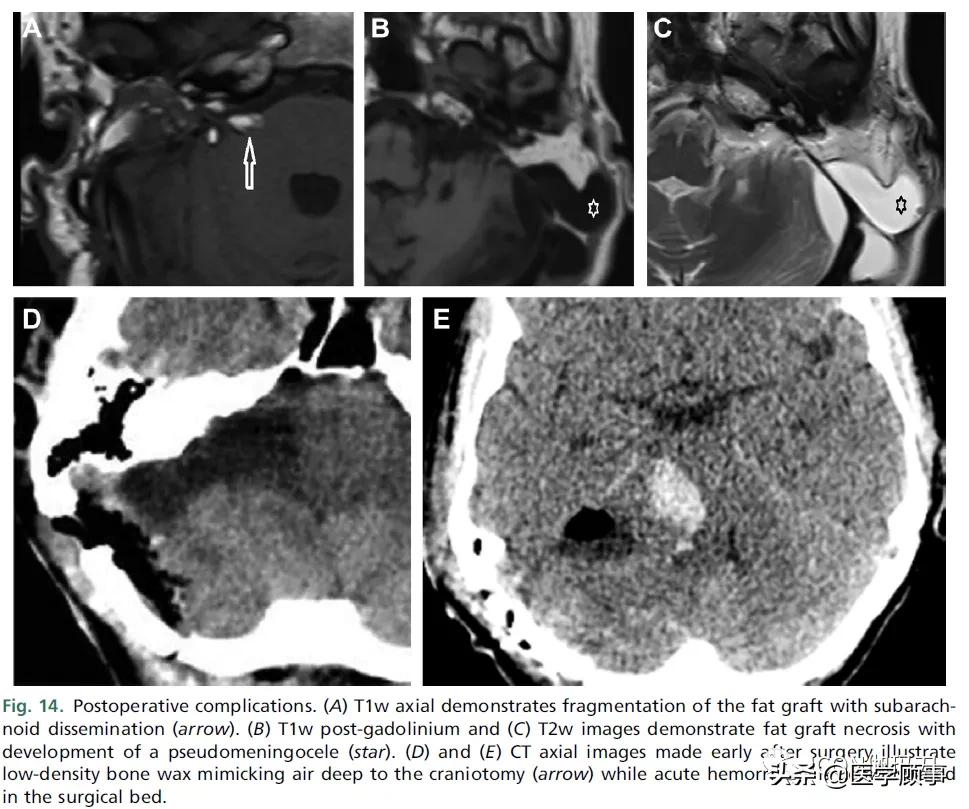

本文描述了每个手术入路的预期术后MRI表现。可能需要影像学检查来评估术后并发症。潜在的术后并发症取决于手术入路(见表6),由于脑脊液漏(和相关的脑膜炎)或脑实质损伤,需要影像学评估。在脑脊液漏(1% - 8%)的情况下,CT和3D T2w MRI可用于识别未封闭的岩骨乳突气房(petro-mastoid air cells)、颅骨切除术边缘或岩尖处的缺口,以及相关的脑脊液逸出(transgression)(图14)。经迷路手术后脂肪移植物坏死(1%)也可能导致易发生脑脊液漏,表现为移植物碎裂和液体浸润(manifests as fragmentation and fluid infiltration of the graft),可能导致类脂性脑膜炎(potential lipoid meningitis)和假性脑膜膨出(pseudomeningocele)。用于密封气房或控制导静脉出血的骨蜡不应被误认为是手术部位或硬脑膜静脉血栓部位的颅内空气(Bone wax used to seal air cells or control bleeding from emissary veins should not be mistaken for intracranial air at the site of surgery or dural venous thrombus.)。脑实质损伤可能继发于动脉或静脉缺血、脑炎或回缩损伤(be secondary to arterial or venous ischemia, cerebritis, or retraction injury)。术后出血(0.6%)可能由静脉损伤引起,尤其是岩静脉桥接,因为几乎所有的大肿瘤都附着于岩静脉(Postoperative hemorrhage (0.6%) may result from venous injury, with particular risk to bridging petrosal veins which are adherent to almost all large tumors.)。也有患同侧硬脑膜静脉窦血栓的风险(5% - 6%)。

图14。术后并发症。(A) T1w轴位示脂肪移植物碎裂,蛛网膜下腔播散(箭头)。(B)钆剂后T1w和(C) T2w显示脂肪移植物坏死并出现假性脑膜膨出(星形)。(D)和(E)术后早期CT轴位图像显示开颅深部低密度骨蜡类似空气(箭头),而在手术瘤床上显示有急性出血。